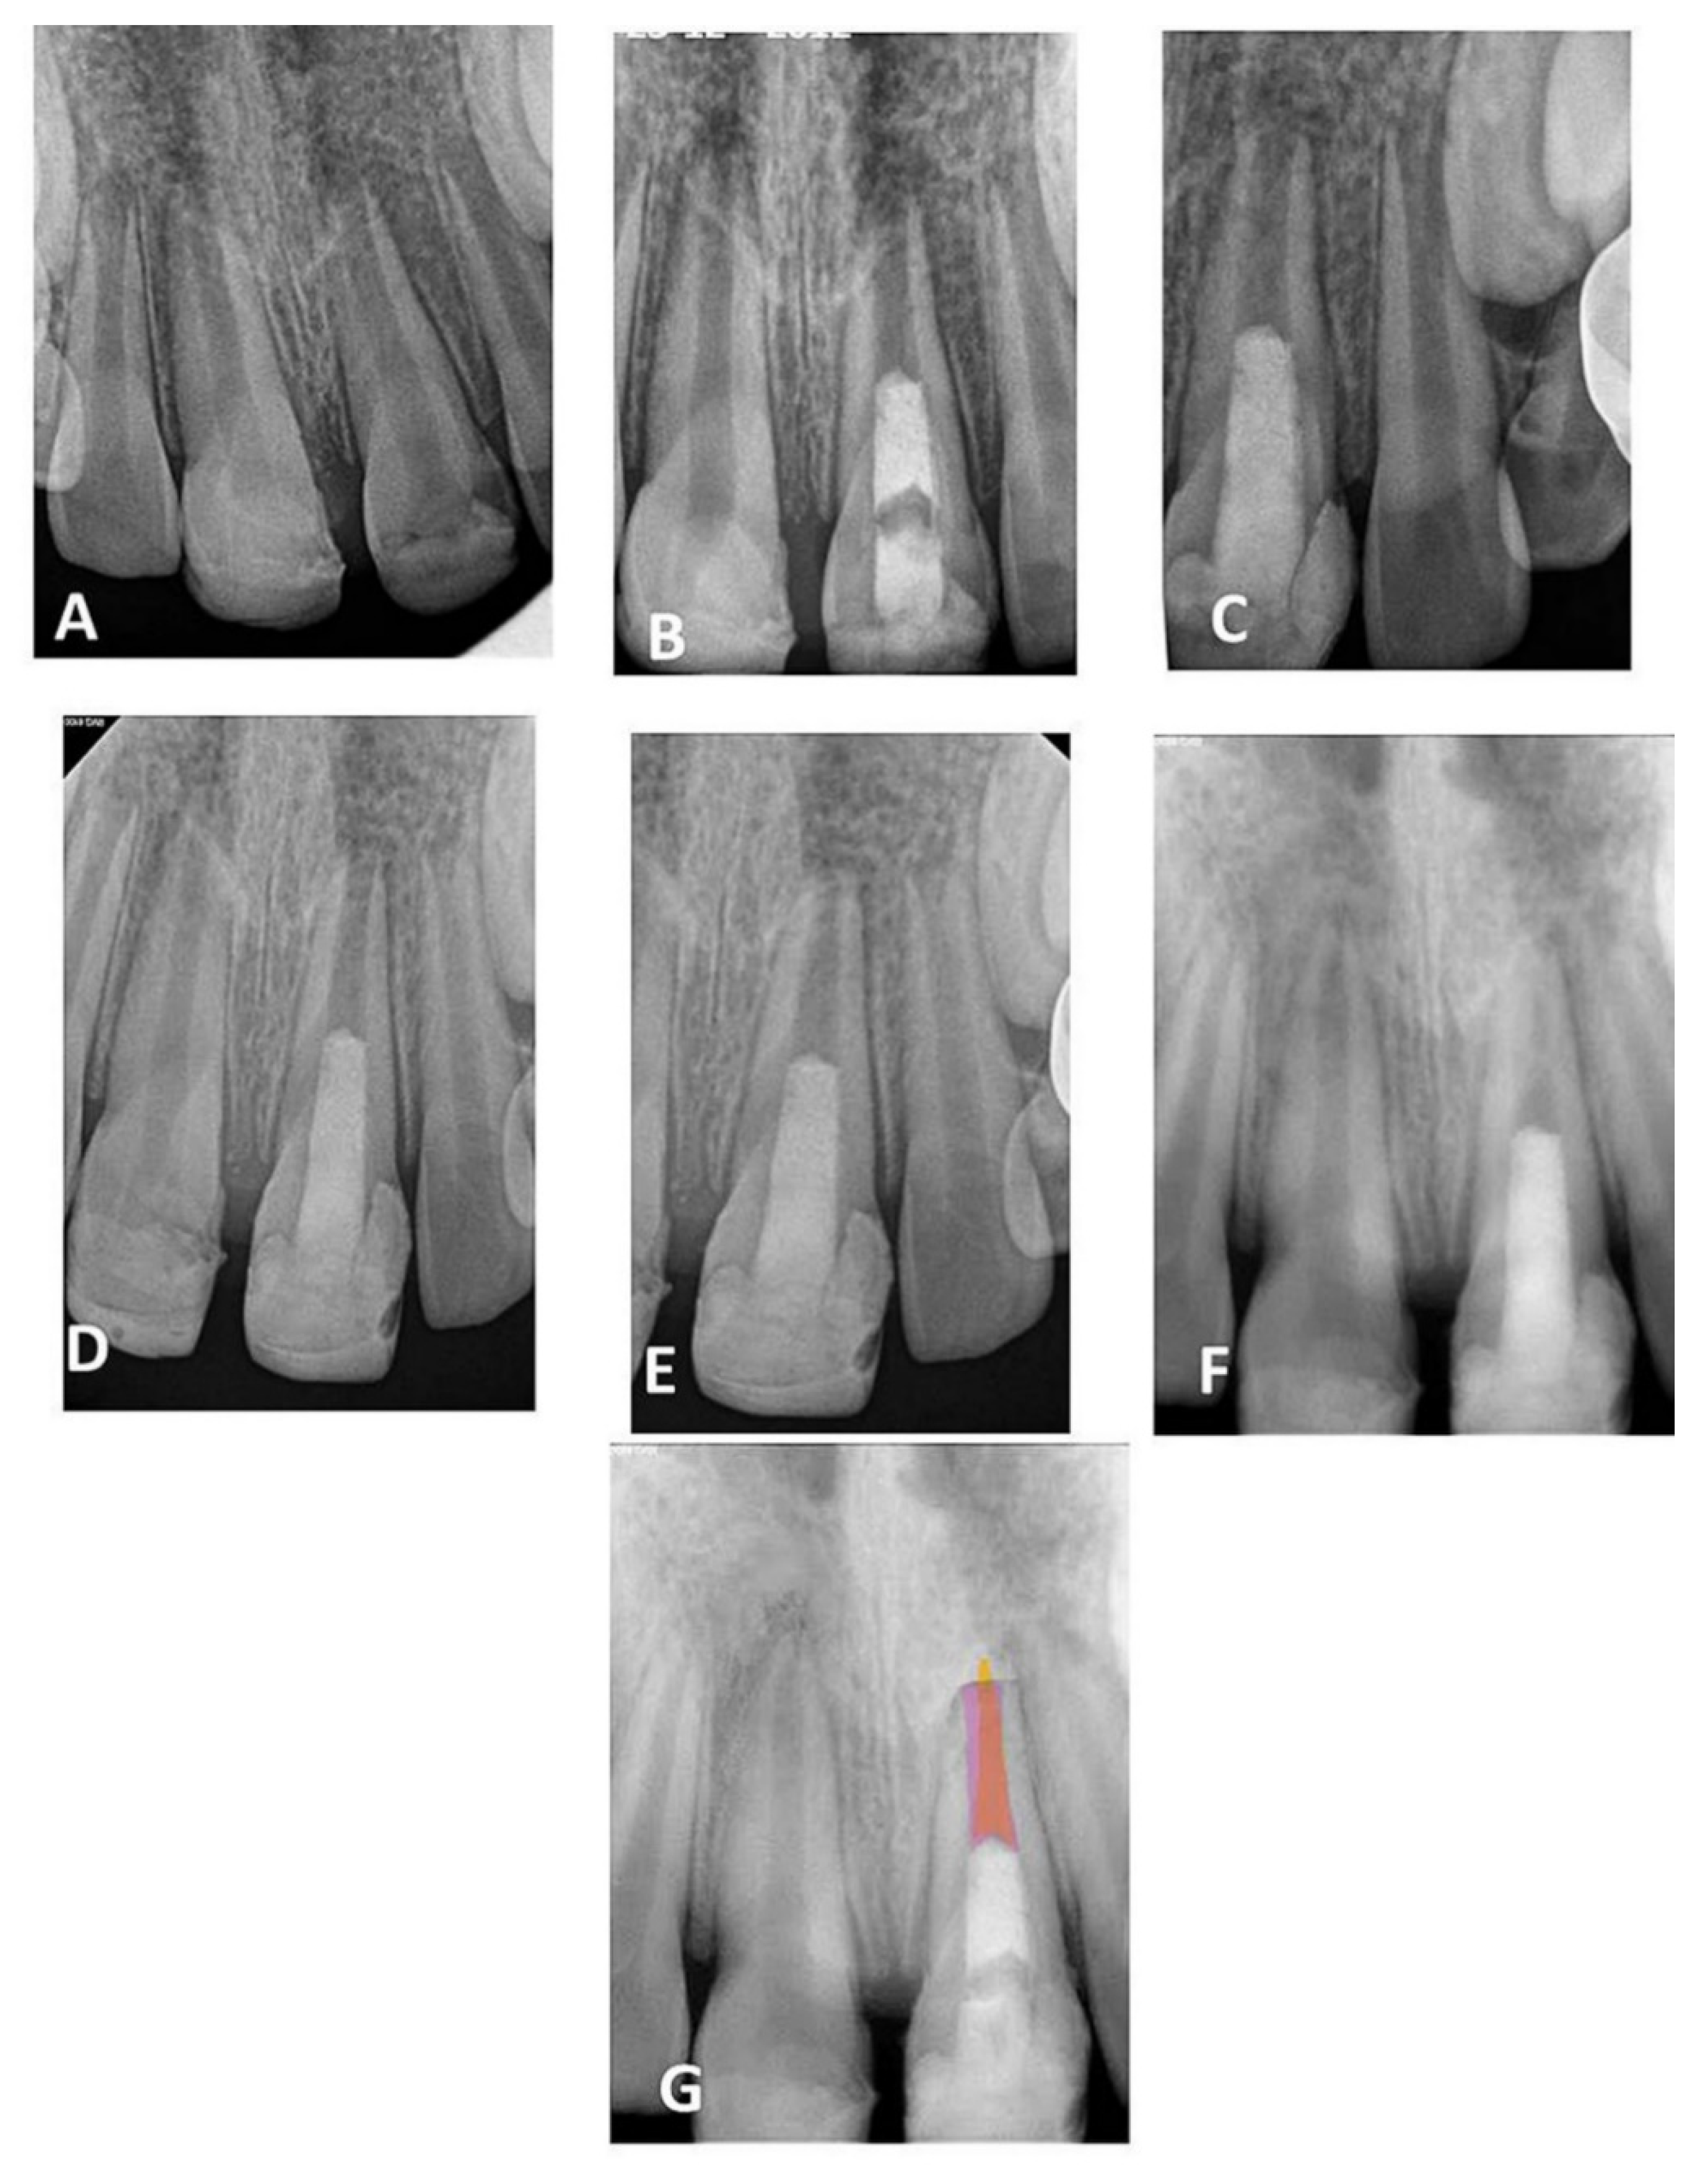

| 9 | Male | 11 | 21 | Trauma | 10.34 | 0.79 | 2.32 | 8 years | 6 | Respond |

| 10 | Male | 11 | 11 | Trauma | 10.02 | 0.51 | 1.85 | 8 years | 6 | Respond |

| 11 | Male | 11 | 11 | Trauma | 10.375 | 0.56 | 1.68 | 8 years | 6 | No Respond |

| 12 | Male | 11 | 11 | Trauma | 10.05 | 0.56 | 1.13 | 8 years | 9 | Respond |

| 13 | Male | 11 | 11 | Trauma | 9.356 | 0.39 | 1.14 | 8 years | 6 | No respond |

| 14 | Male | 13 | 31 | Trauma | 9.40 | 0.31 | 1.233 | 8 years | 6 | No respond |

| 15 | Male | 11 | 21 | Trauma | 9.338 | 0.38 | 1.15 | 8 years | 9 | Respond |

| 16 | Male | 9 | 35 | Caries | 9.40 | 0.31 | 1.16 | 8 years | 6 | Respond |